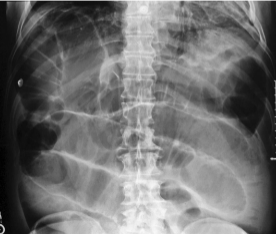

Blockage of bowel lumen

bowel obstruction

Failure of bowel peristalsis

ileus